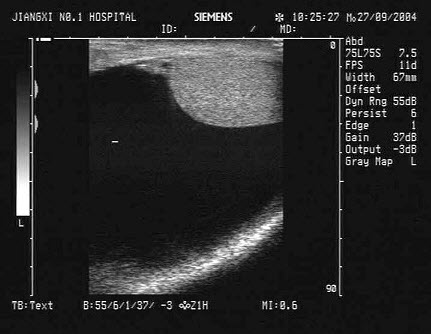

20、单项选择题

女,25岁,因急性胰腺炎禁食5天。声像图如图所示。结合超声声像图,诊断为()

A.胆囊泥沙样结石

B.胆囊内胆汁淤积

C.胆囊多发性息肉

D.胆囊多发性胆固醇结晶

E.胆囊癌

21、单项选择题